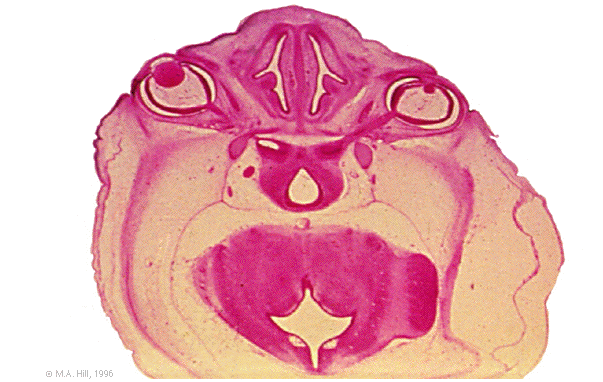

Hum B1